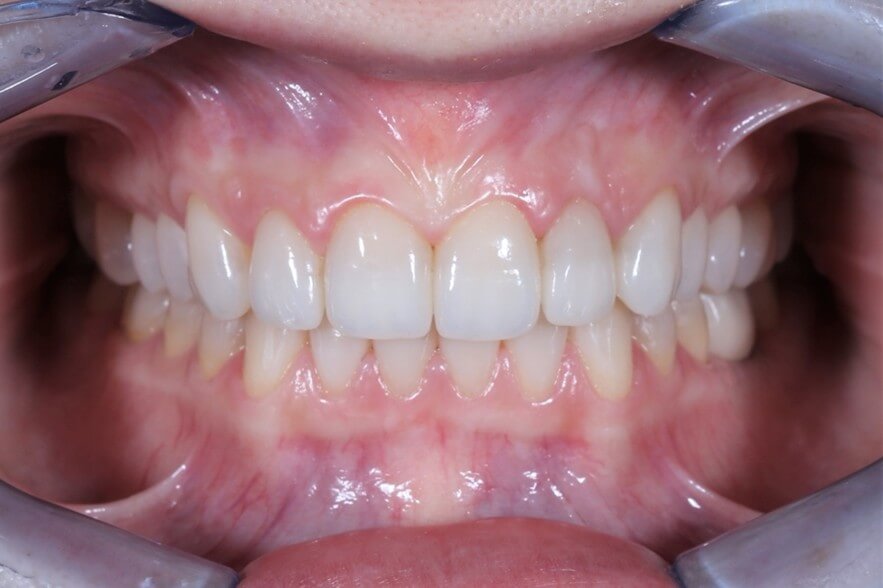

Η πλήρης αποκατάσταση στόματος (γνωστή και ως full mouth rehabilitation ή full mouth reconstruction) είναι μια οδοντιατρική διαδικασία που στοχεύει στην πλήρη αποκατάσταση της λειτουργίας, της αισθητικής και της υγείας ολόκληρου του στόματος, σε περιπτωσεις που εχουν όλα αυτά χαθεί.

Περιλαμβάνει τη συνδυασμένη θεραπεία και αποκατάσταση όλων ή σχεδόν όλων των δοντιών και συχνά των ούλων και των περιριζικών ιστών, των αρθρώσεων της γνάθου και της σύγκλεισης.

Κλινικές Περιπτώσεις